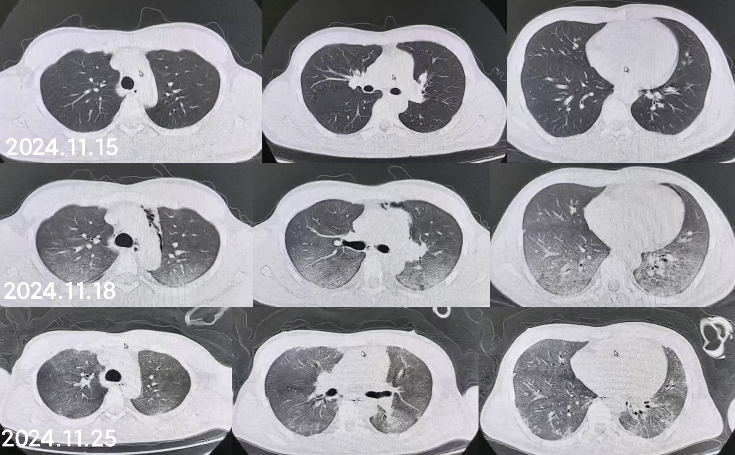

同时给予镇痛、镇静联合肌松,去甲肾上腺素泵入维持血压,俯卧位通气,B某入院后出现高热,经验性给予美罗培南联合万古霉素抗感染治疗,后降阶梯调整为哌拉西林他唑巴坦联合万古霉素治疗;C某抗感染方案为经验性使用万古霉素联合哌拉西林他唑巴坦治疗,痰培养出鲍曼不动杆菌后改为替加环素、头孢哌酮舒巴坦及万古霉素治疗;根据《刺激性气体中毒诊治专家共识》[5]中关于重症患者的治疗措施,同时给予2人泮托拉唑抑酸护胃,氨溴索、富露施化痰、甲泼尼龙抗炎、西维来司他纳及乌司他丁清除炎性介质,维生素C抗氧化、保肝、输血补液,纤支镜吸痰及肺泡灌洗,维持水电解质平衡及营养支持治疗,特别考虑到肺损伤情况,在使用有创通气时给予超保护性通气策略[5, 7];2人仍先后出现气胸、纵膈气肿,行胸腔闭式引流;持续V-V ECMO治疗15 d后,肺部纤维化不可逆转,高分辨率CT肺纤维化评分 > 75%(图 3、4),符合终末期肺病标准,有肺移植指征[8],经评估后2人顺利完成病变肺组织切除(图 5),双侧序贯肺移植,术后患者复查胸片肺部恢复正常(图 6),2位患者术后气管切管接呼吸机辅助通气,并给予泼尼松、他克莫司、吗替麦考酚酯抗排异治疗,其余根据病情给予万古霉素调节肠道菌群、抗感染、保肝、抗凝、呼吸康复锻炼等治疗,后顺利脱机、拔除气切套管,病情稳定出院,后续规律复查胸部CT(图 7)恢复良好。

| 注:图A为B某;图B为C某 图 6 患者肺移植术后胸片 |

| 注:图A为B某;图B为C某 图 7 肺移植术后第2个月、5个月、8个月CT影像 |